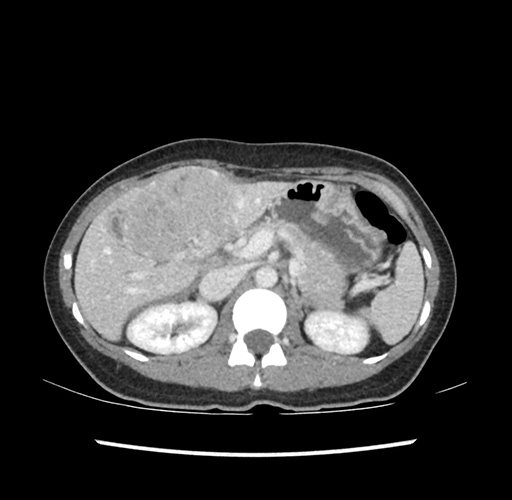

Imaging Analysis

Look through the patient's CT scan to identify any areas of concern for the necessary procedure.

Based on your CT findings, which issue(s) would give reason for "planned slowing down moment(s)" in this case?

Considering a standard left lateral sectionectomy procedure, what step(s) of the operation would you do differently in this case ?